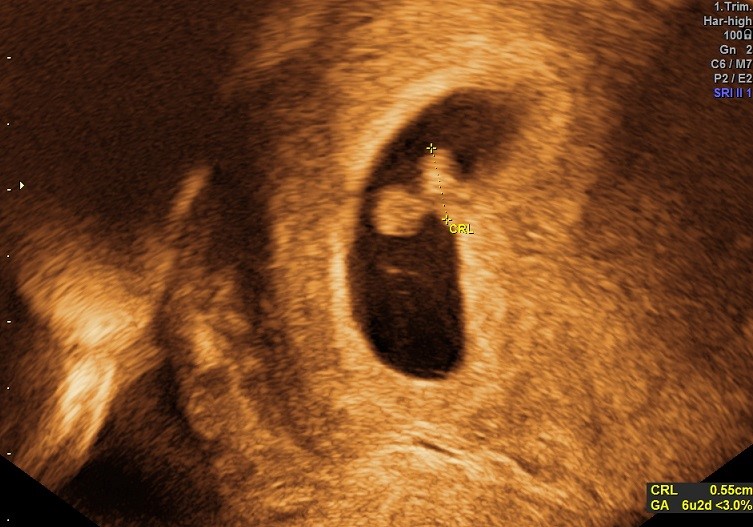

Er bare så glad og lykkelig! Betalte mig fra en "nysgerrighedsscanning" i dag, som viste den fineste lille babyreje med en ordentlig madpakke

Er blevet sat 4 dage tilbage i cyklus (eller 4 dage frem om man vil), så hvad jeg troede var 6+6 er blevet rykket til 6+2, og dermed termin 28. maj. Men det undrer mig egentlig ikke, for min cyklus har altid været lidt svigende. Hørte hjertelyd og så hjerteblink, og det var bare så fint! Nu synes jeg tiden til nf føles endnu længere, haha!